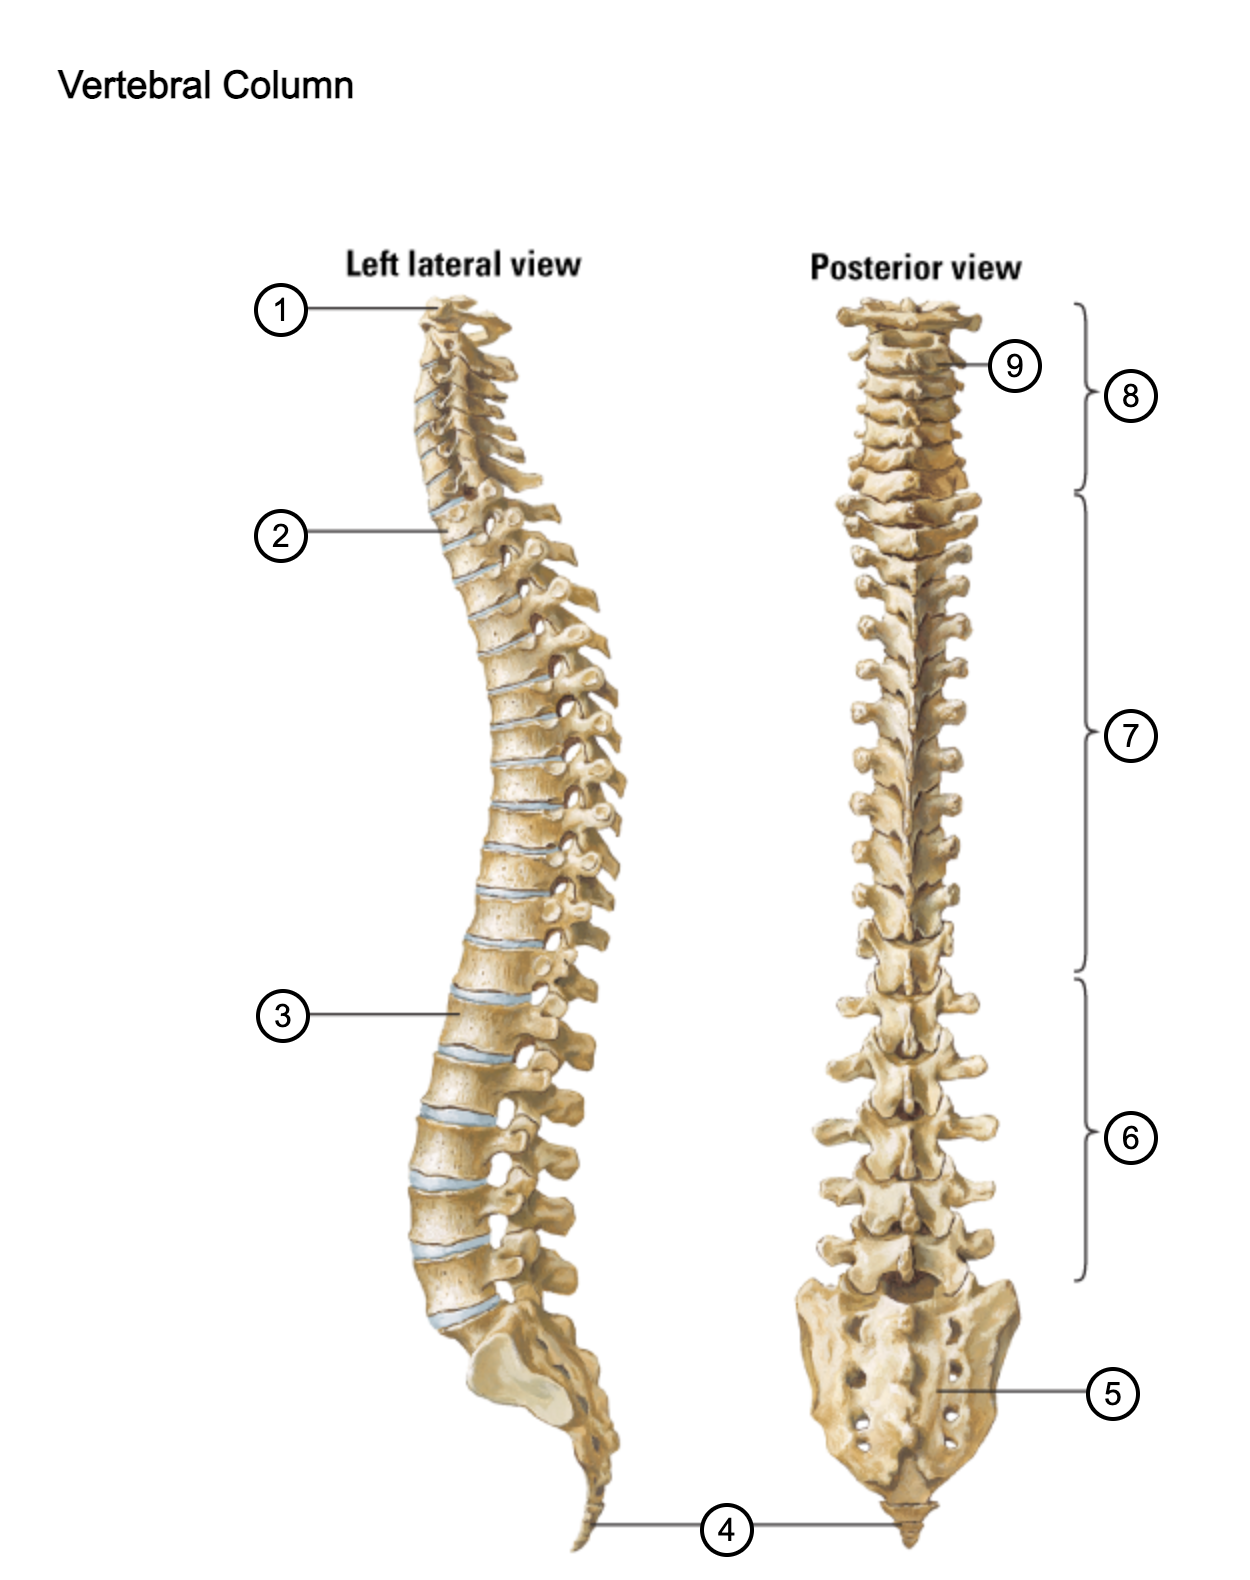

1

atlas (C1)

2

T1

3

L1

4

coccyx

5

sacrum (S1-5)

6

lumbar vertebrae

7

thoracic vertebrae

8

cervical vertebrae

9

axis (C2)